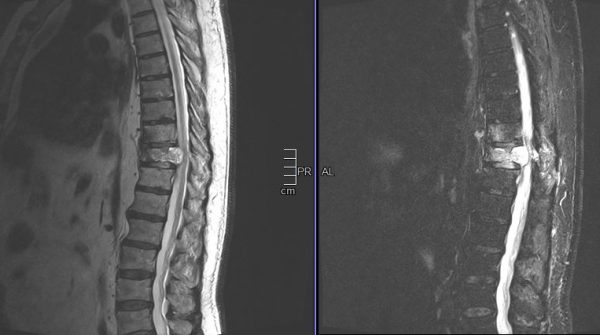

Παράδειγμα εξωσκληρίδιου όγκου: Ασθενής Άρρεν, 73 ετών, με γνωστή μεταστατική μάζα στον Θ10 σπόνδυλο, η οποίοα προκαλεί σημαντική στένωση του σπονδυλικού σωλήνα και πίεση επί του νωτιαίου μυελού. Διενεργήθη αποσυμπίεση του νωτιαίου μυελού και διαδερμική σπονδυλοδεσία/σπονδυλοπλαστική Θ9-Θ10. Μετεγχειρητικά ο ασθενής ανέφερε σημαντική πίεση του άλγους του και σημαντική βελτίωση της βάδισης.

(Προσωπικό Αρχείο Νευροχειρουργού Π. Σταυρινού)